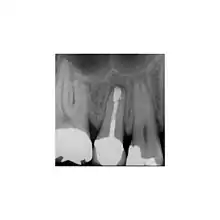

une infection bactérienne de la dent visible sur la radiographie dentaire